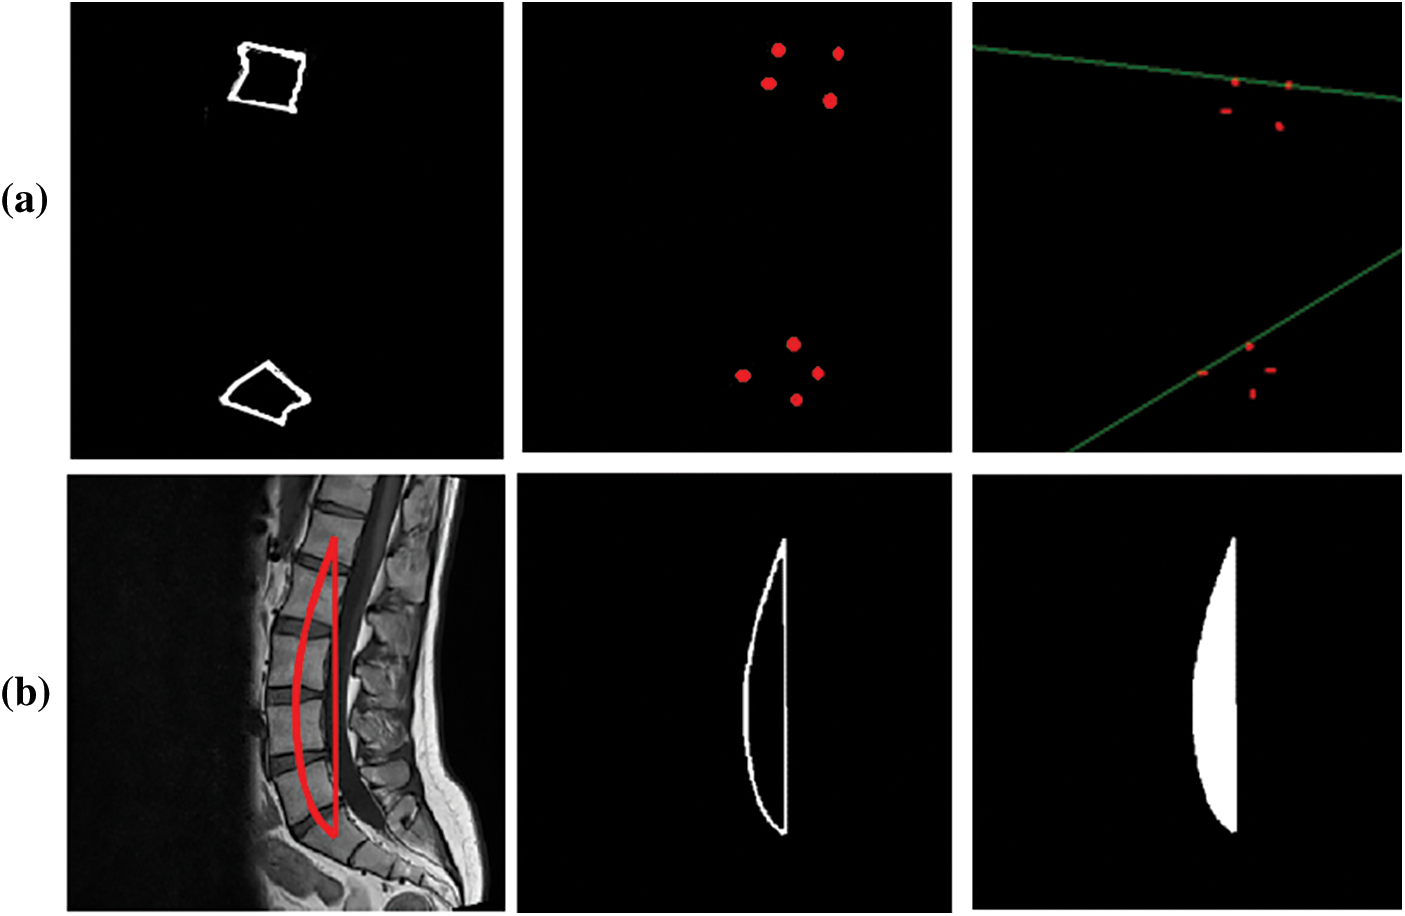

Fig. 7 shows the Cobb estimation techniques. Here, (a) represent the edges detected, from these edges corner points are calculated. The proposed method of Cobb estimation from corner points is presented where L1 and S1 vertebrae are shown. On the other hand, (b) depicts the process of AUC where center-line curvature is formulated and a perpendicular is dropped. Thus, this creates an enclosed region for classification of Lordosis.

Figure 7: Cobb results (a) Corner point method (b) AUC method